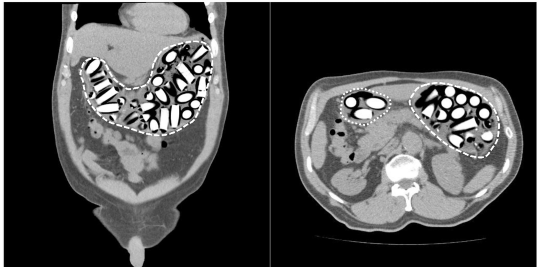

La radiografía de abdomen al ingreso mostró múltiples imágenes radiopacas en el marco cólico sugestivas de cuerpos extraños (Figura 1). Se solicitó una tomografía computarizada (TC) de abdomen con contraste en la cual se describieron hallazgos compatibles con síndrome pilórico secundario a retención gástrica de cuerpos extraños, sin evidencia de tránsito hacia distal (Figura 2). Fue llevado a laparotomía exploratoria identificando marcada distensión de la cámara gástrica; se realizó una gastrotomía y extracción sin complicaciones de 97 cuerpos extraños de látex en forma de dedo con pérdida del recubrimiento de parafina (Figura 3).

En caso de diagnóstico inconcluso con alta sospecha clínica, la TC de abdomen puede ser de gran utilidad con una sensibilidad y especificidad superiores al 95 % 5. La TC simple puede brindar más información, teniendo en cuenta que el medio de contraste puede interferir con la visualización de los paquetes 5,7. Dependiendo de la pureza del narcótico existen diferentes patrones de atenuación; la cocaína que constituye la sustancia más frecuentemente transportada, por lo general es isodensa con la materia fecal, mientras que la marihuana suele ser hiperdensa y la heroína hipodensa 5.